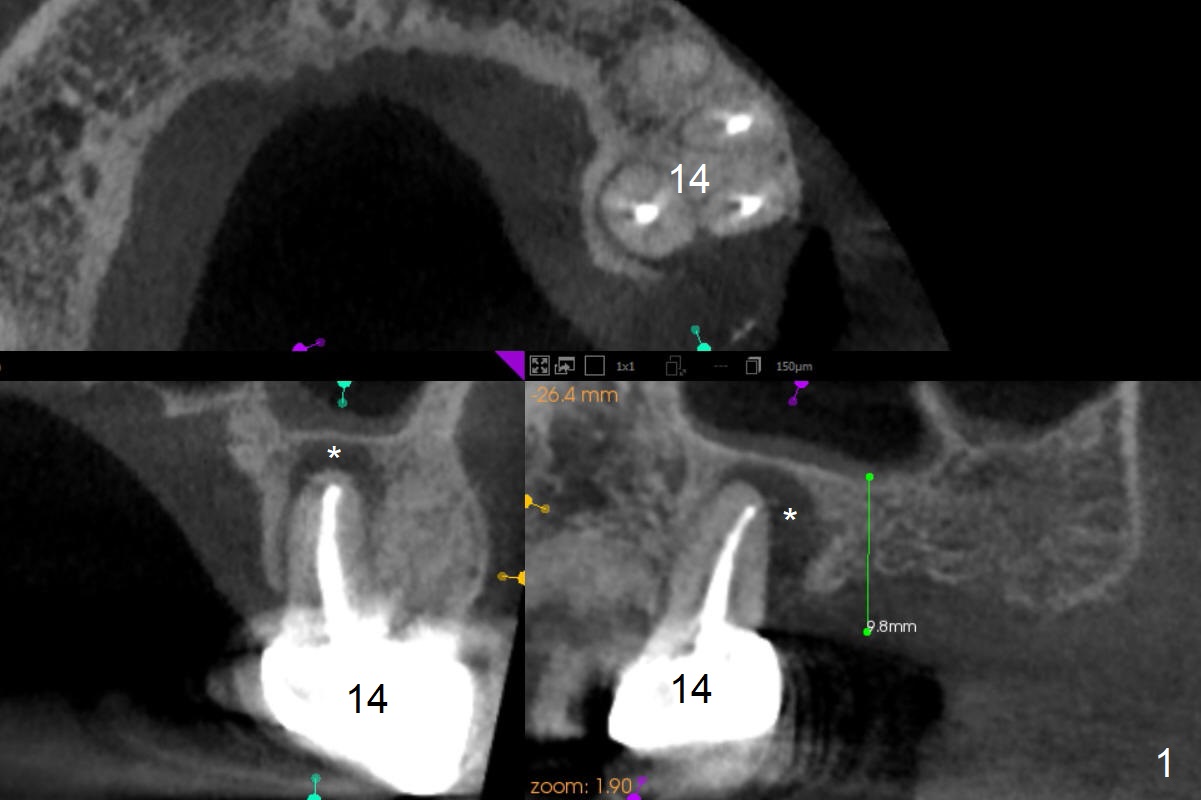

A 53-year-old man cannot chew on the left side with distal abscess in spite of RCT for #14 (* in Fig.1,2 (taken 11 ad 21 months postop, respectively)). After extraction (Fig.3 (CBCT coronal section) black area), start osteotomy with 2 mm drill (red outline) in the septum buccal to the palatal (P) socket). Following 2 mm drill removal (Fig.4), use 4.3 mm Magic Drill (red outline) for ~ 9 mm. When the osteotomy is being done, the osteotomy most likely shifts palatal (Fig.5 arrow) because of thin bone palatally. When the MD is removed (Fig.6), use Magic Sinus Lifter (Fig.7 pink) for sinus lift (arrow). The implant is to be 5x11 mm or larger. Because of the distal defect (Fig.1,2), start osteotomy mesially. Take Alginate impression before surgery for possible orthodontic treatment. Since bone density is high, use higher voltage and longer time for X-ray.